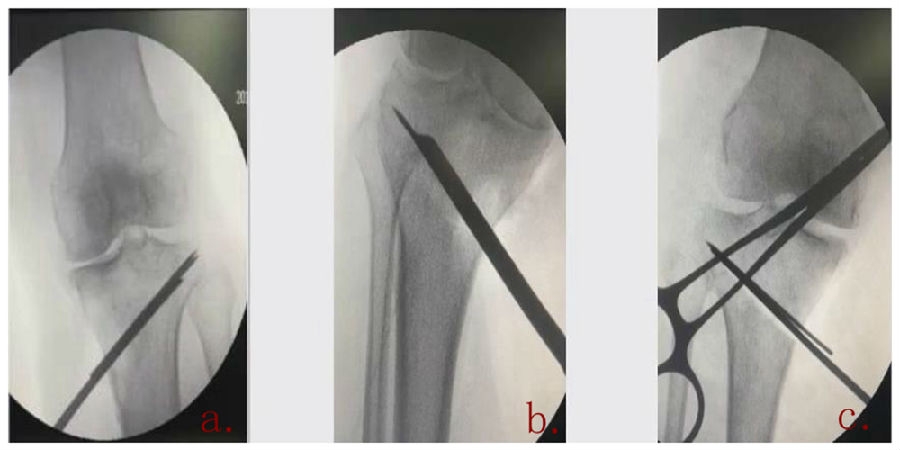

(2)Ⅱ型骨折

当出现Ⅱ型骨折时要特别注意,因为此时截骨的远端就是骨折的远端,近端只有上胫腓周围骨筋膜存在,所以相对来说Ⅱ型骨折并不稳定。

首先用拉力螺钉复位,调整好力线。然后做结构性植骨,延迟负重,所谓延迟负重就是延迟到外侧合页和上行截骨线处达到初始愈合,然后再让患者进行负重。如果不做结构植骨加延迟负重,就会出现一些非常严重的现象,如不愈合。

拉力钉复位,结构性植骨

左侧患者未植骨正常负重,术后4个月不愈合;右侧患者非结构性植骨过早负重,术后1年未愈合